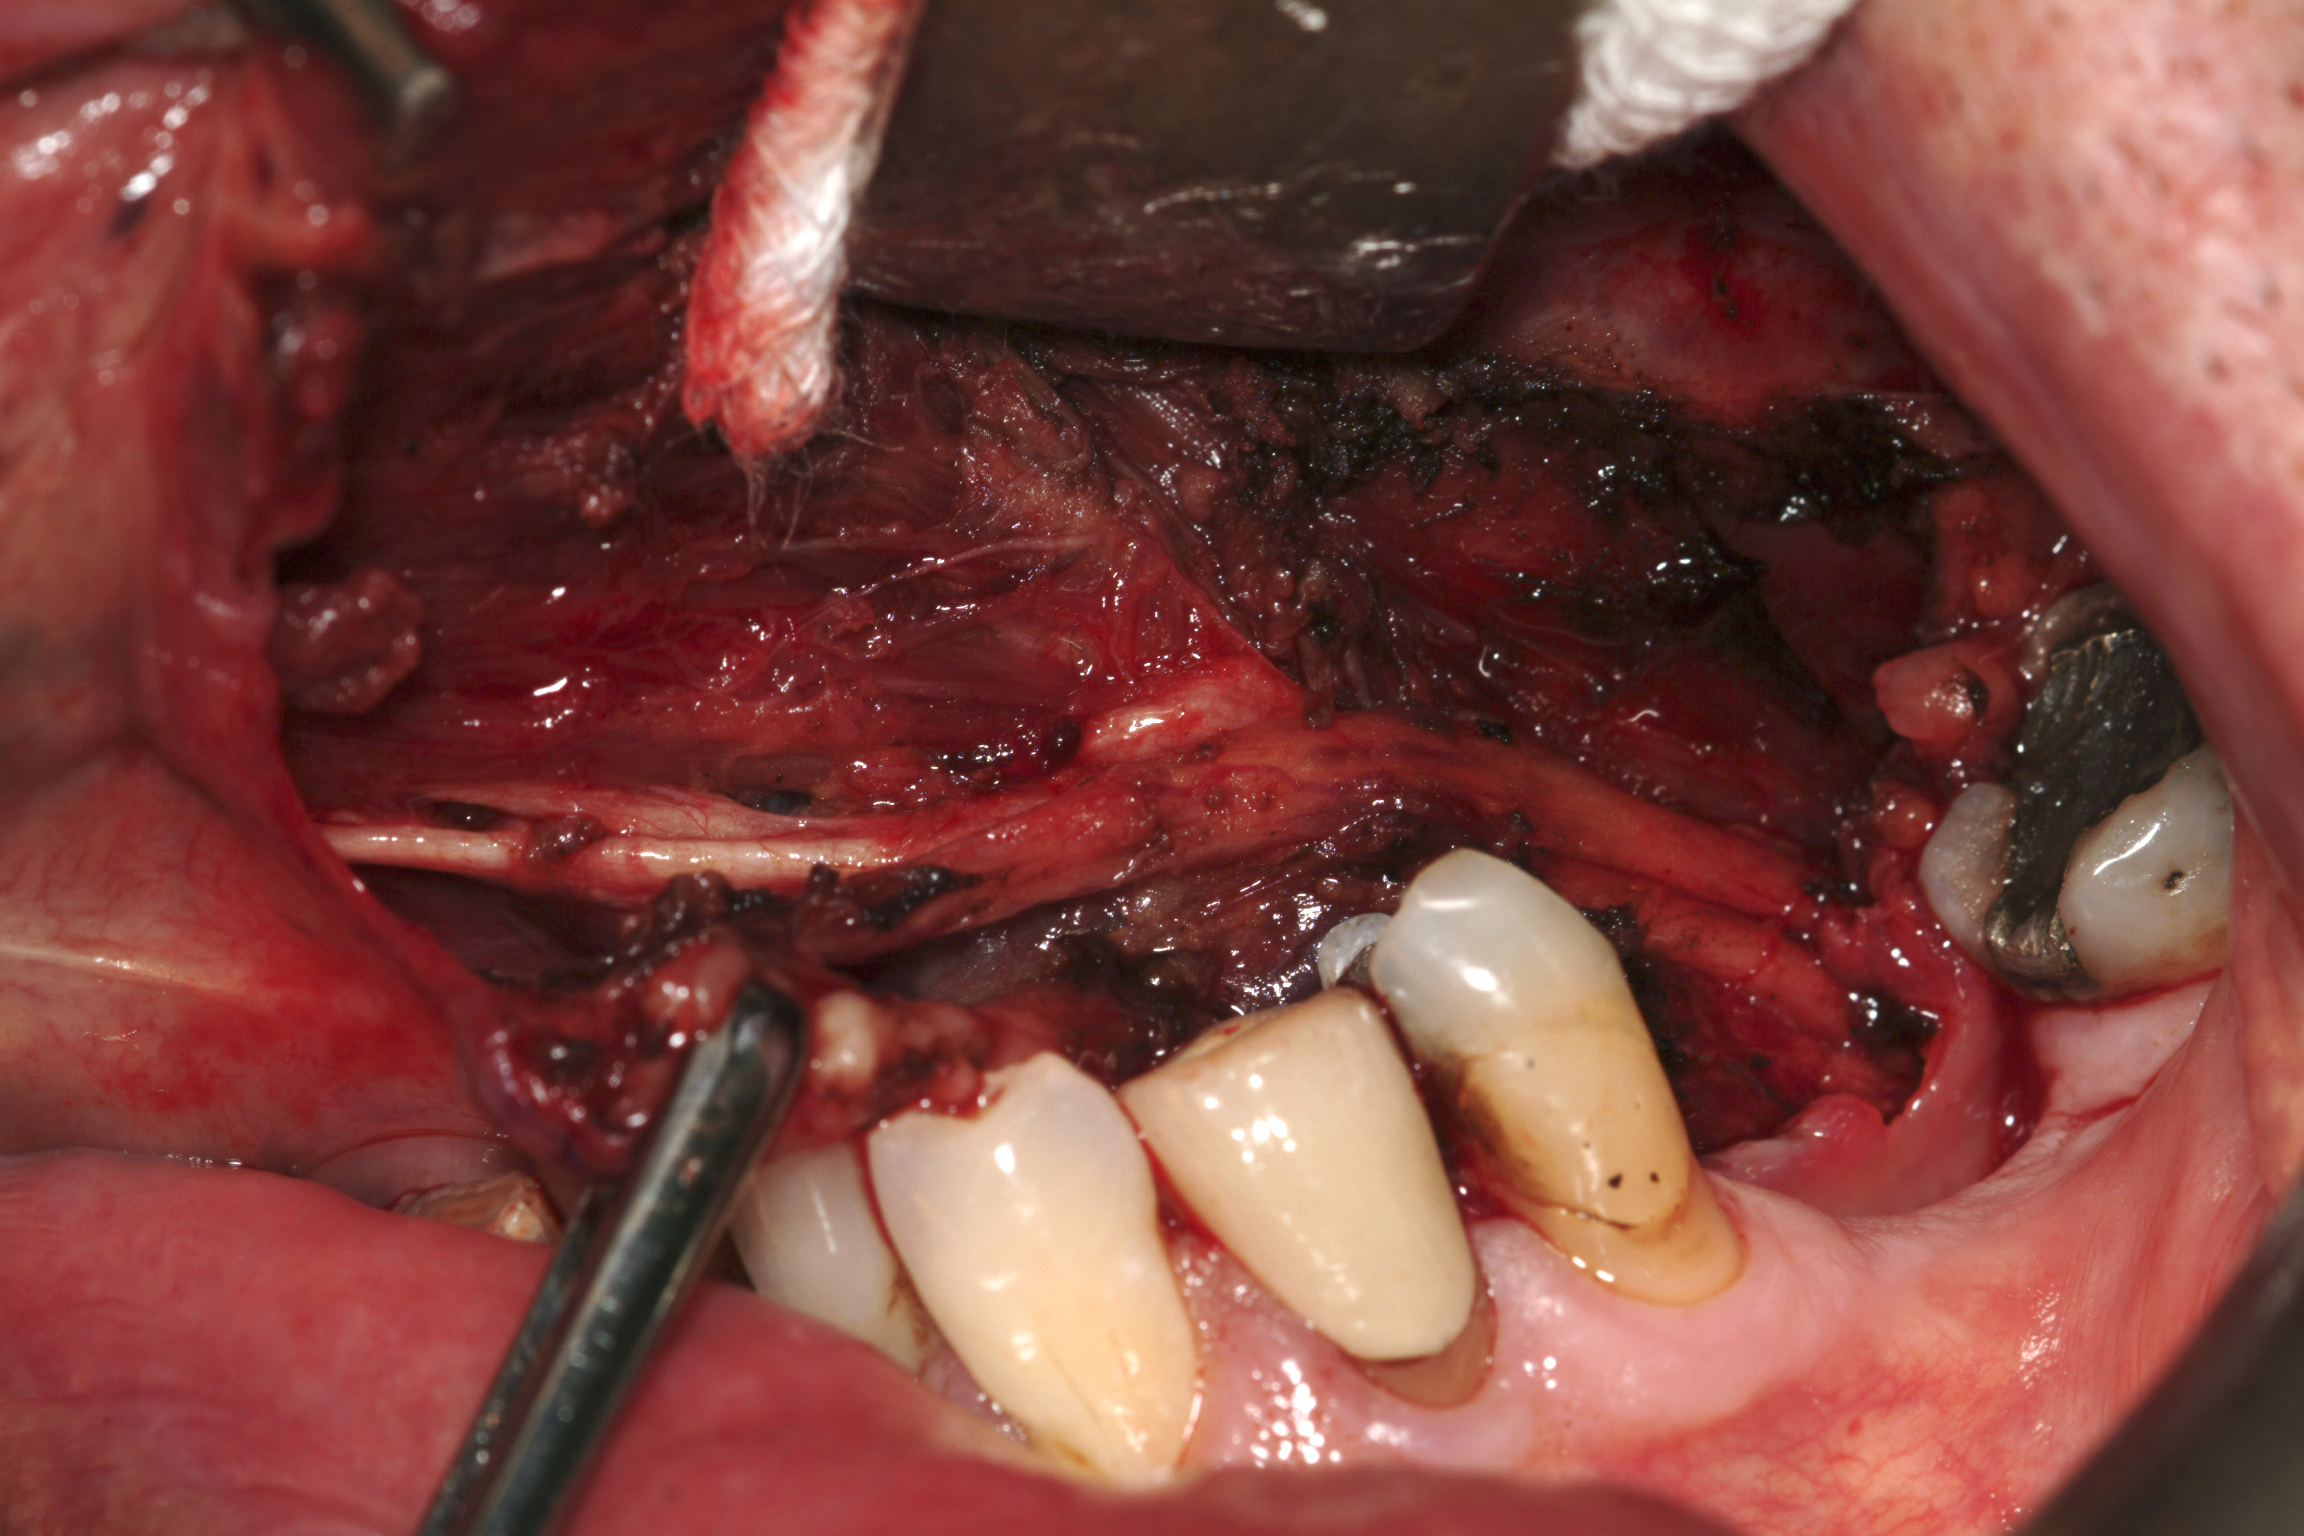

Within the parotid gland, the facial nerve branches into an upper and lower division from which stem the five named major branches. The nerve separates the gland into its superficial and deep lobes (see Figure 2). There is no natural tissue plane here and the nerve should be thought of as being embedded in the substance of the gland. Also within the gland are the retromandibular vein, external carotid artery, lymph nodes and filaments from the auriculotemporal nerve.

Figure 2: The facial nerve embedded in the parotid glandular tissue. Although it is said that the facial nerve separates the gland into ‘deep’ and ’superficial’ lobes, there is no fascial compartmentalisation.